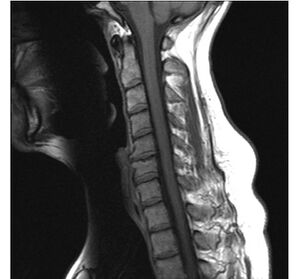

image الإنجليزية

Cervical Spine MRI showing degenerative changes.jpg

٩٦٠ × ٨٩٢؛ ٩٥ كيلوبايت